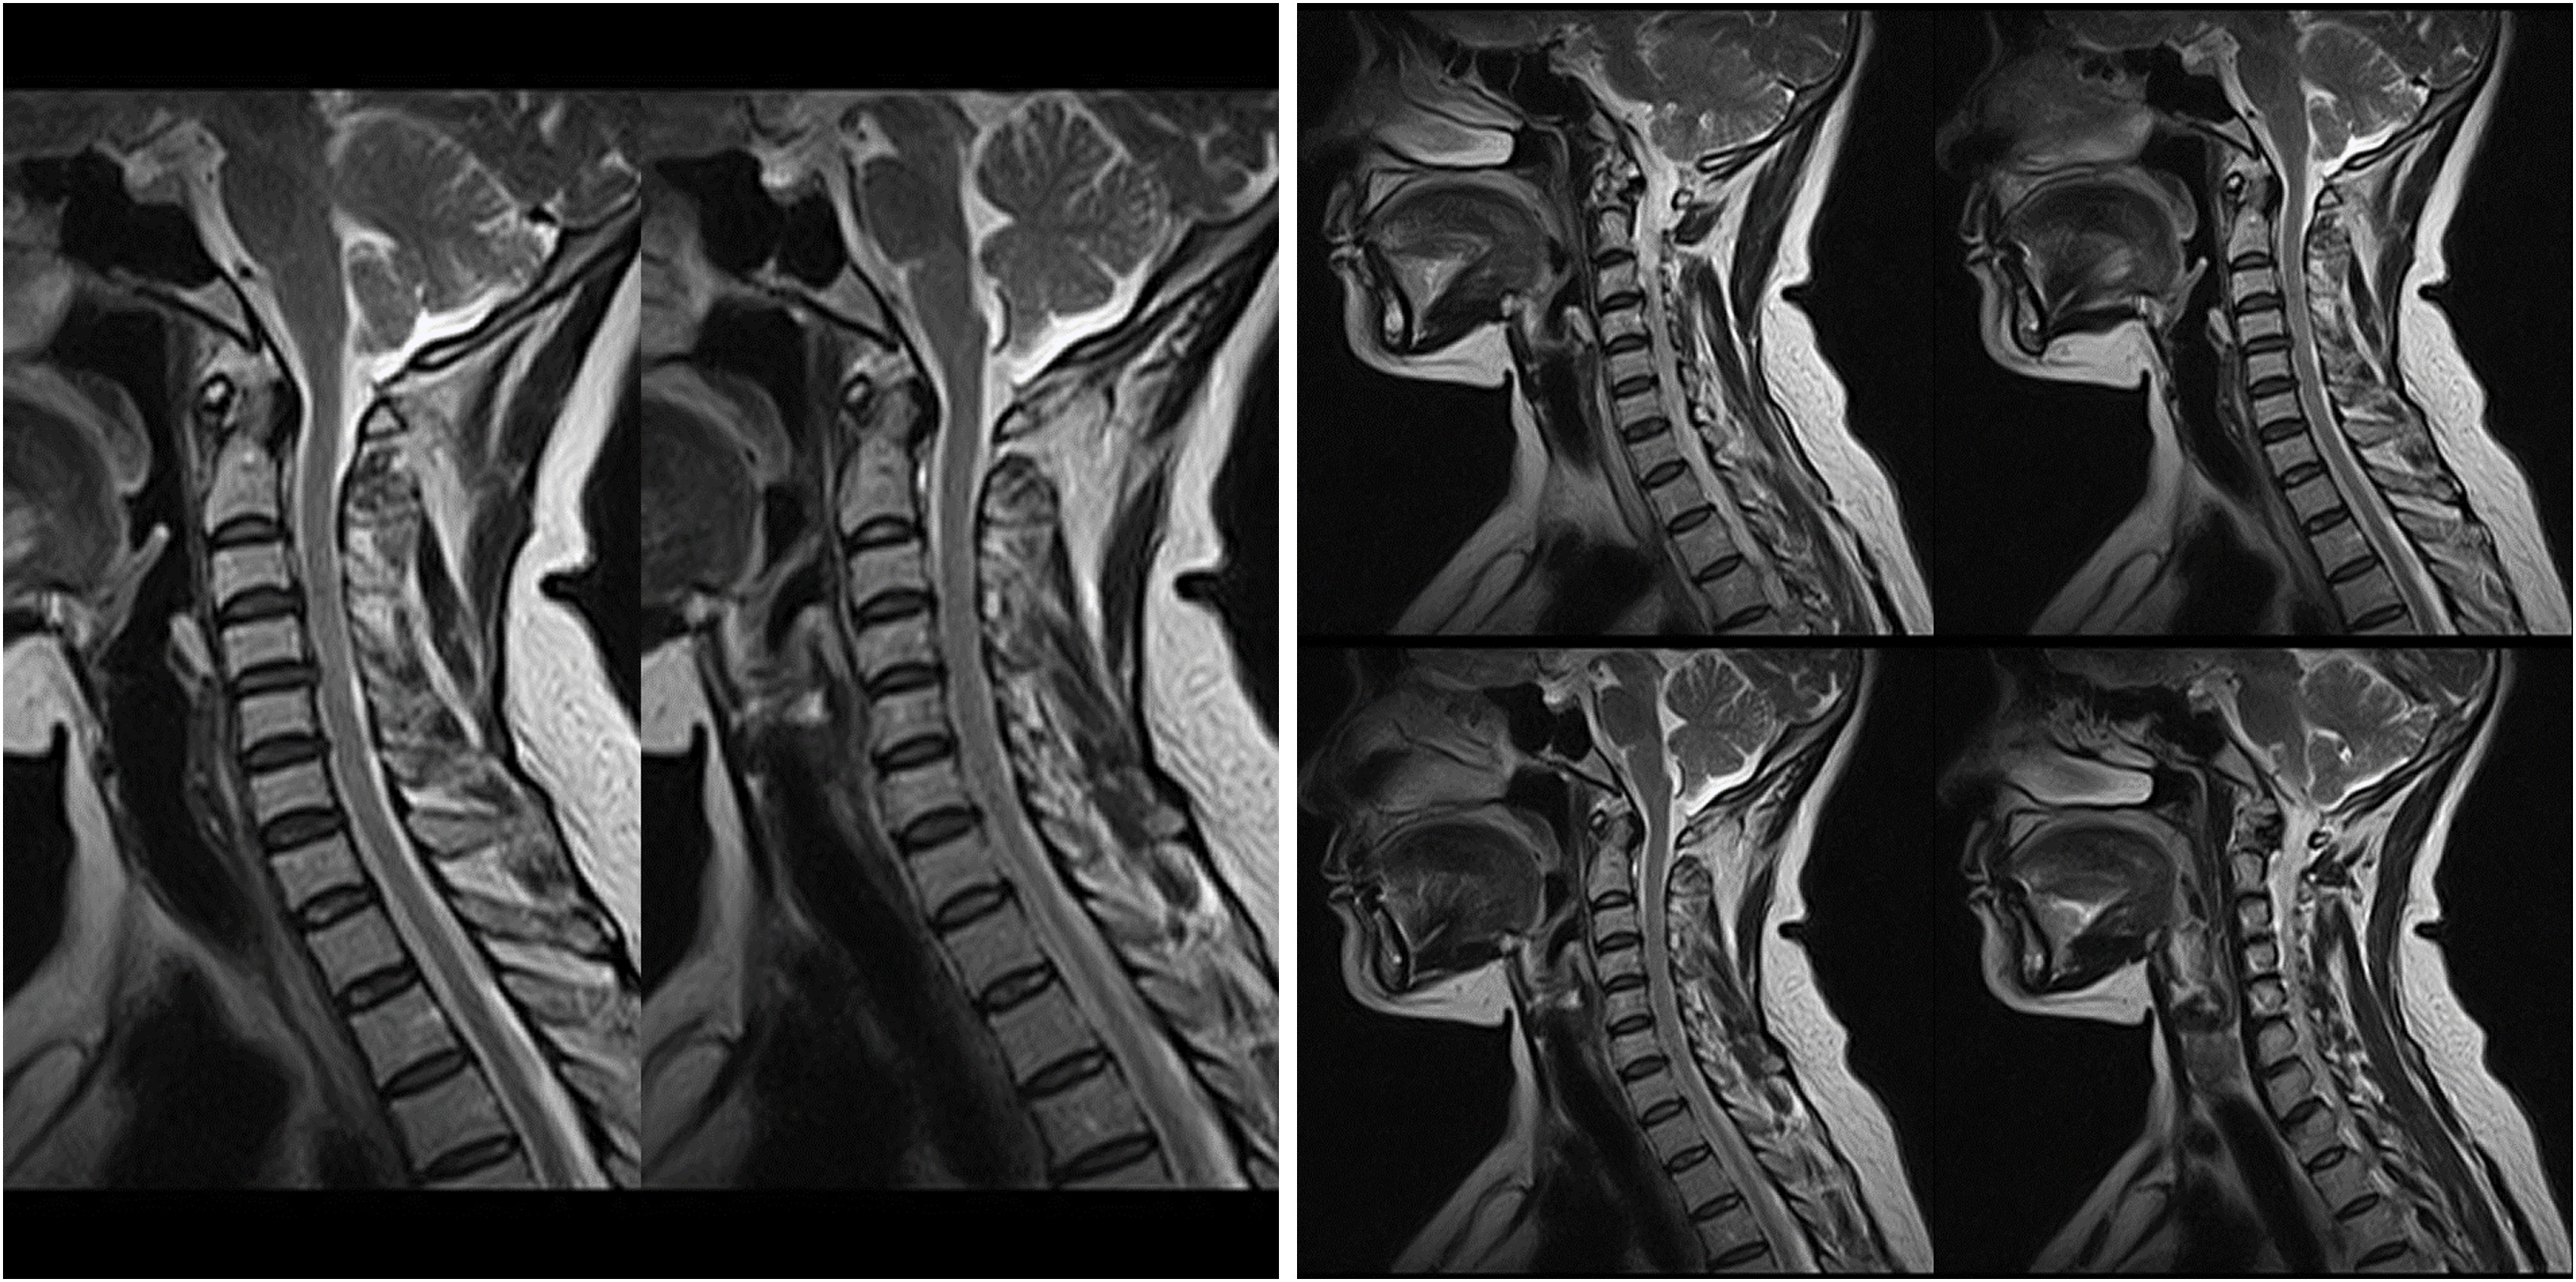

Hình ảnh lâm sàng

Giải pháp lâm sàng ấn tượng